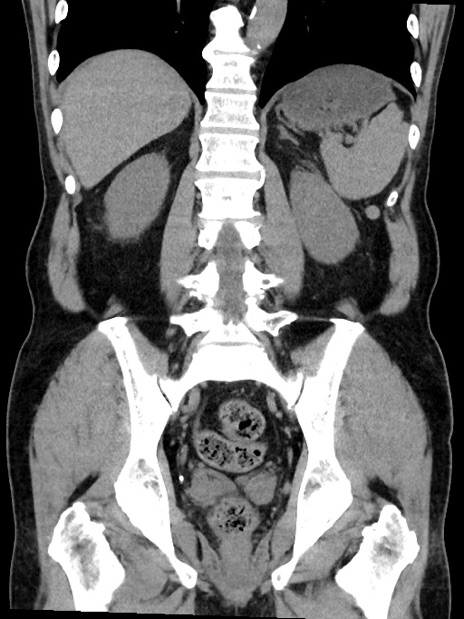

症例35(冠状断像)

【症例】70歳代 男性

【主訴】腹部膨満、嘔吐

【現病歴】昨日より腹部膨満感出現。本日増悪し、仙痛出現。嘔吐あり、受診。

【既往歴】糖尿病、胆摘後

【身体所見】BP 149/80mmHg、HR 74/min、BT 35.9℃、腹部:膨満、軟、圧痛なし。腸雑音減弱あり。上腹部正中切開瘢痕あり。

【データ】WBC 13500、CRP 1.72